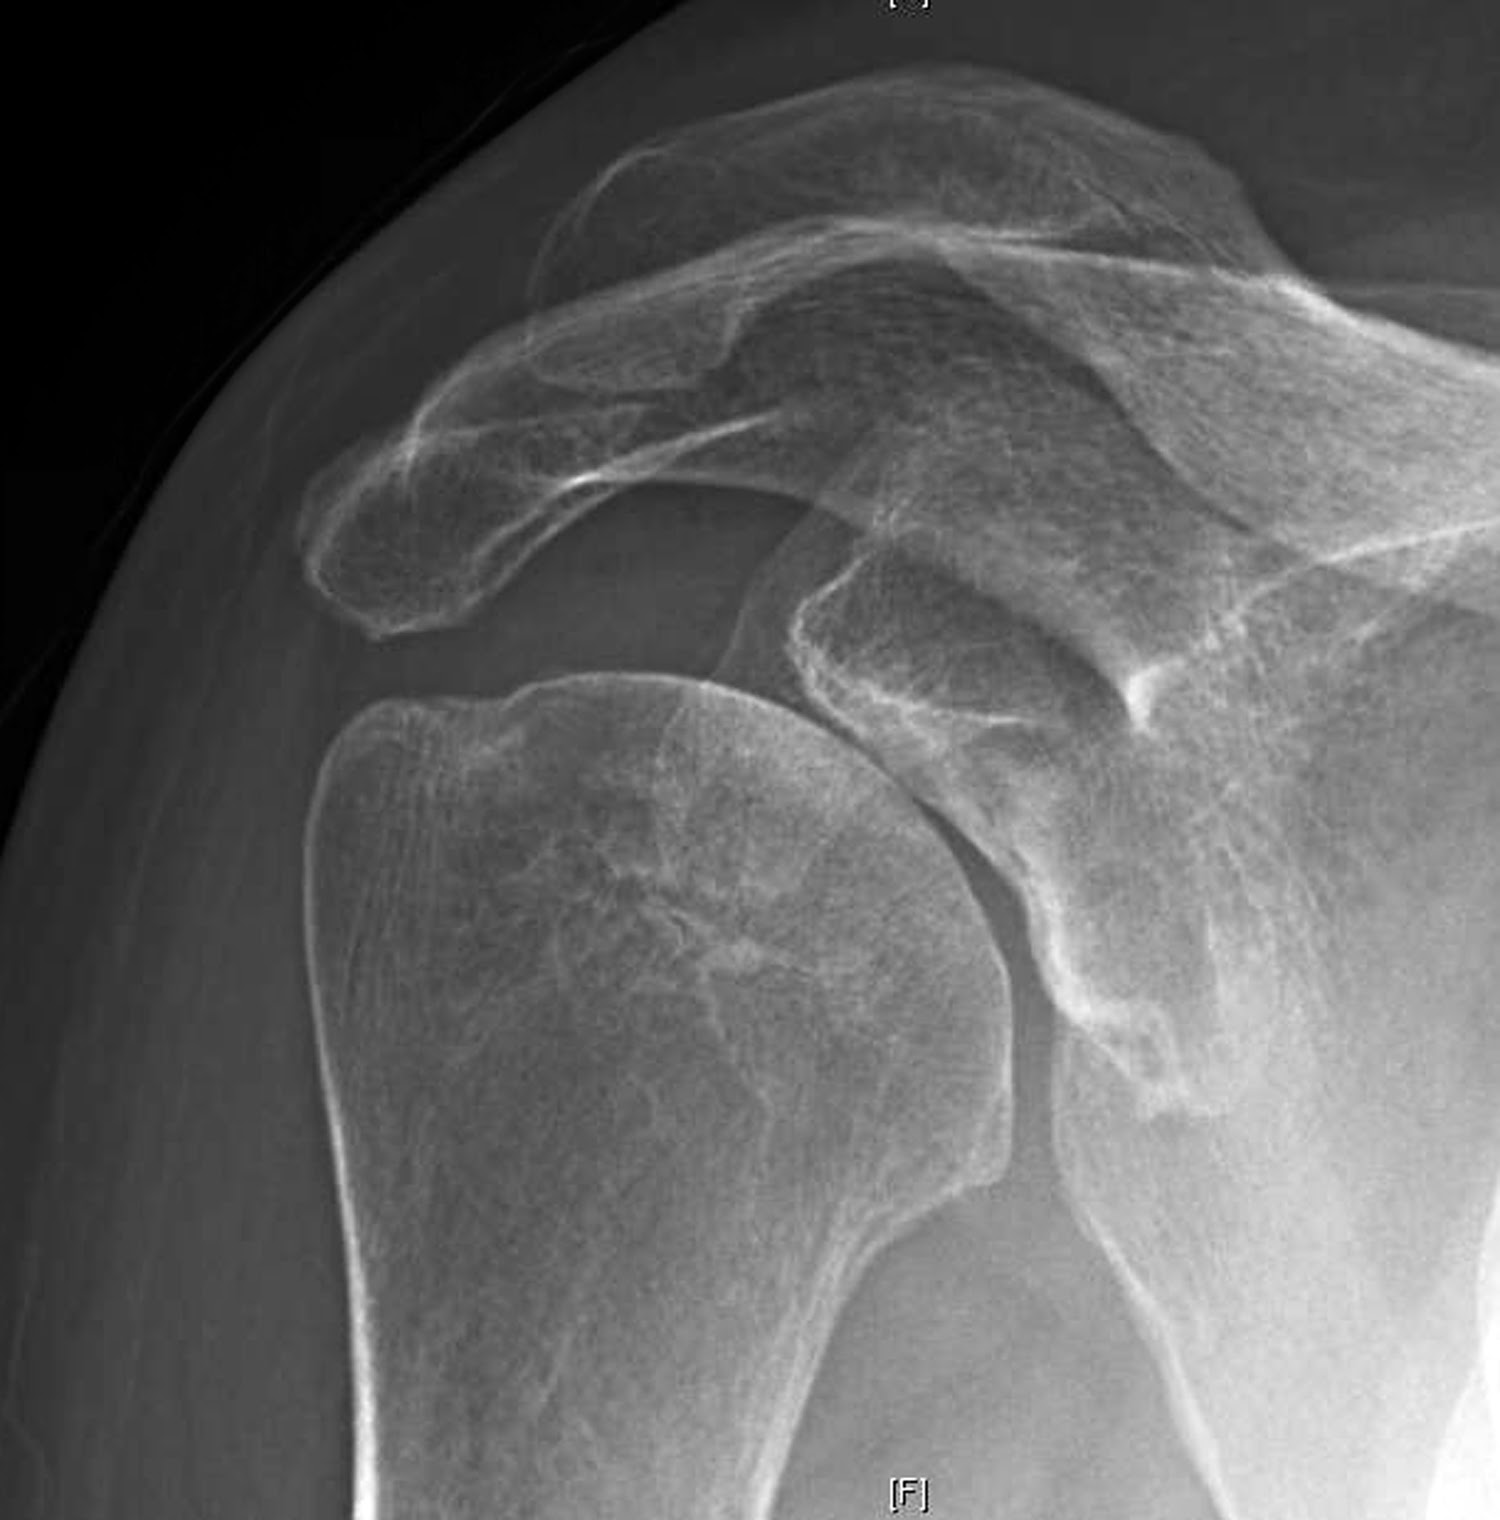

The first key view is the anteroposterior in the plane of the scapula taken so that the x-ray beam passes through the glenohumeral joint. This view shows the superior-inferior position of the humeral head relative to the glenoid, the presence of osteophytes on the humeral head and glenoid, joint space narrowing, the degree of medial displacement of the humerus in relation to the lateral acromial line, the quality of the humeral and glenoid bone, the presence of loose bodies, and the presence of humeral head collapse or deformity.

When taken properly, the standardized anteroposterior and axillary views indicate the thickness of the cartilage space between the humerus and the glenoid, the relative positions of the humeral head and the glenoid, the presence of osteophytes, the degree of osteopenia, and the extent of bony deformity and erosion.